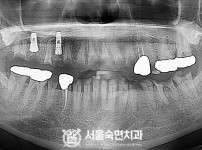

임플란트-전후사진1

임플란트-전후사진2